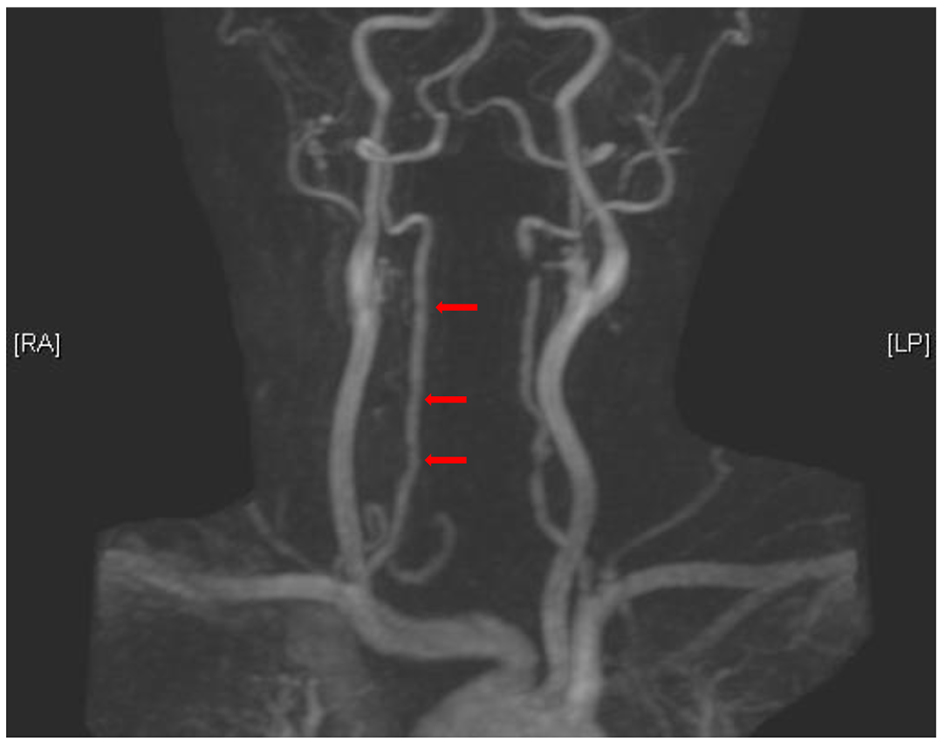

To clarify, on initial presentation, the patient we described had multifocal dissections in left vertebral artery (C2/3 and C6 level), best visualized with time-of-flight technique (arrows in Fig. 1), while gadolinium-enhanced imaging suggested stenosis in the left vertebral artery, and also multifocal regions of irregularity/narrowing in the right vertebral artery best visible on gadolinium-enhanced imaging (arrows in Fig. 2). Our patient would be classified as multiple vascular bed involvement on the basis of the above-mentioned findings. Follow-up imaging 15 months after the initial presentation (performed after submission of the case report) showed healed dissection areas in the left vertebral artery with worsening diffuse narrowing in the right vertebral artery (arrows in Fig. 3). Patient discontinued all prescribed medications except ASA, between 4 and 15 months after the initial event by her own choice. She remained clinically asymptomatic.

![]() Click for large image | Figure 1. Multifocal dissection in left vertebral artery (C2/3 and C6 levels). |